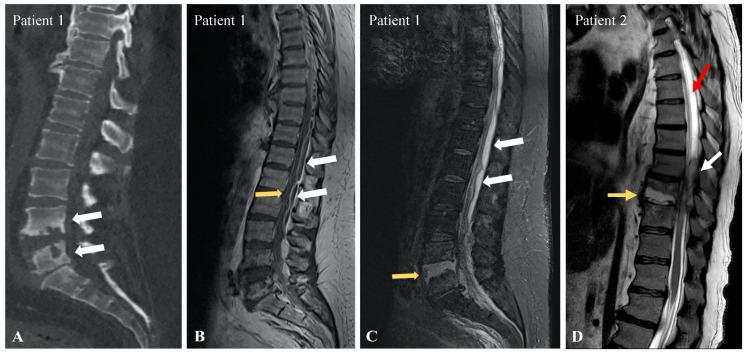

We describe two patients who suffered from Froin's syndrome secondary to spinal abscesses. According to our review, FS is caused by neoplasia in 33% of cases, non-malignant mechanical causes in 27%, infections in 27%, non-infectious inflammatory processes in 6%, and vascular in 6%. The most prevalent symptoms are paraplegia/paraparesis (64%), back pain (38%), altered mental state and/or confusion (23%), sciatica (17%), headaches (17%), leg sensory defects (17%), and urinary retention (14%), and are thought to be linked with the underlying causes rather than the CSF characteristics. FS holds a poor prognosis: only 22% recuperate fully after treatment, 22% die due to the cause leading to FS, and 14% retain sequelae.

我们描述了两名继发于脊柱脓肿的弗洛因综合征患者。根据我们的综述,FS在33%的病例中由肿瘤形成引起,27%由非恶性机械性原因引起,27%由感染引起,6%由非感染性炎症过程引起,6%由血管性原因引起。最常见的症状是截瘫/轻截瘫(64%)、背痛(38%)、精神状态改变和/或意识模糊(23%)、坐骨神经痛(17%)、头痛(17%)、腿部感觉缺陷(17%)和尿潴留(14%),并且认为这些症状与潜在病因有关而非脑脊液特征。FS预后较差:仅22%的患者在治疗后完全康复,22%因导致FS的病因死亡,14%留有后遗症。